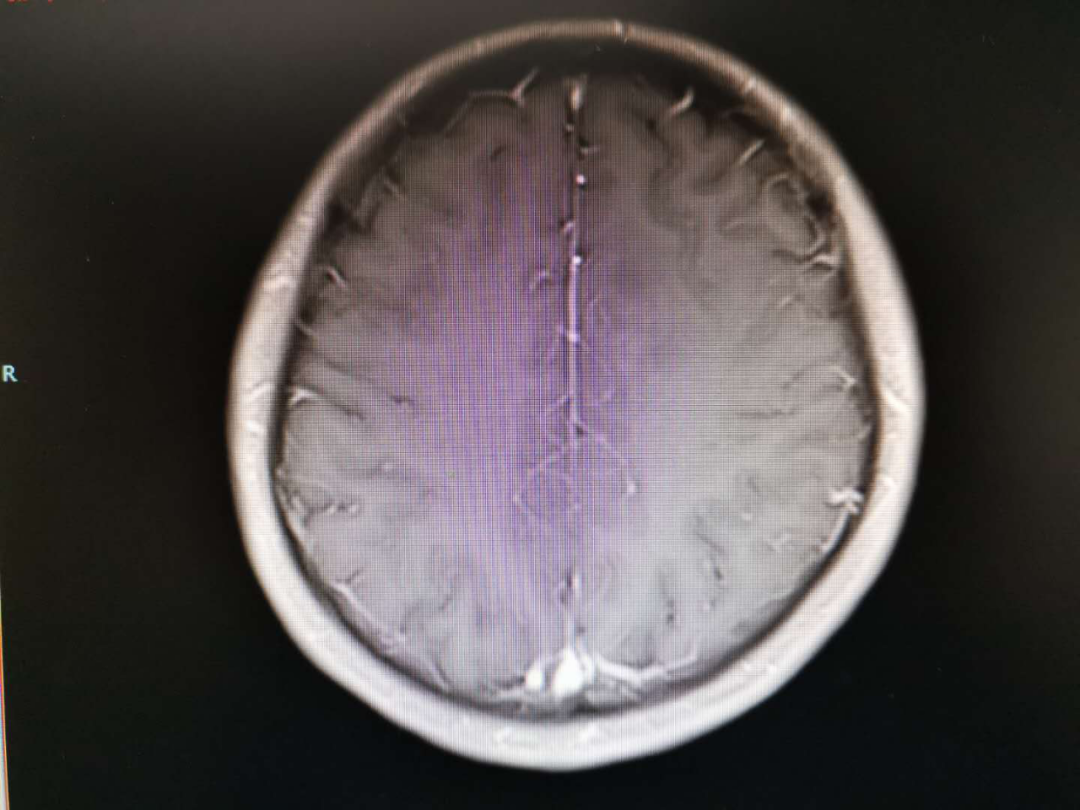

术后放疗处方剂量:PTV1:59.92Gy/2.14Gy/28F,PTV2:50.40Gy /1.80Gy/28F。

放疗范围

2020-01-06放疗后MRI